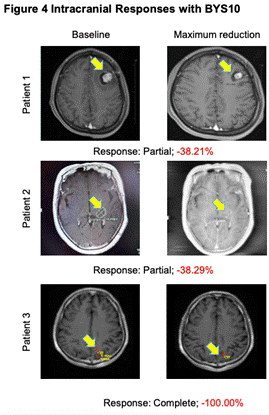

高效入脑:BYS10治疗伴脑转移RET突变实体瘤实现颅内缓解

研究人员在4例至少有1个可测量颅内病灶(1例颅内完全缓解)的患者中观察到颅内抗肿瘤活性。

图4.颅内抗肿瘤活性

从本次ASCO大会所公布的高选择性RET抑制剂BYS10公布了首项Ⅰ/Ⅱ期人体研究结果来看,BYS10在RET实体瘤治疗领域具有非常大的潜力:首先,安全性结果充分表明,BYS10治疗RET突变实体瘤的安全性良好,3-4级TRAE及严重不良反应的发生率低,利于患者长期管理。其次,初步疗效数据结果显示,患者治疗后的ORR为62.5%,DCR为85%,这表明近三分之二的患者经过BYS10治疗能够有效实现疾病缓解,超过五分之四的患者能够实现疾病控制,尤其TC和MTC患者的DCR可达到100%。在临床上更为常见的NSCLC患者中,BYS10治疗的ORR能够达到60%,DCR能够达到80%,充分展现了BYS10的治疗潜能。此外,对于临床上十分关注的脑转移患者,经BYS10治疗后可实现颅内病灶的有效缓解,证实了BYS10的颅内病灶控制潜能。